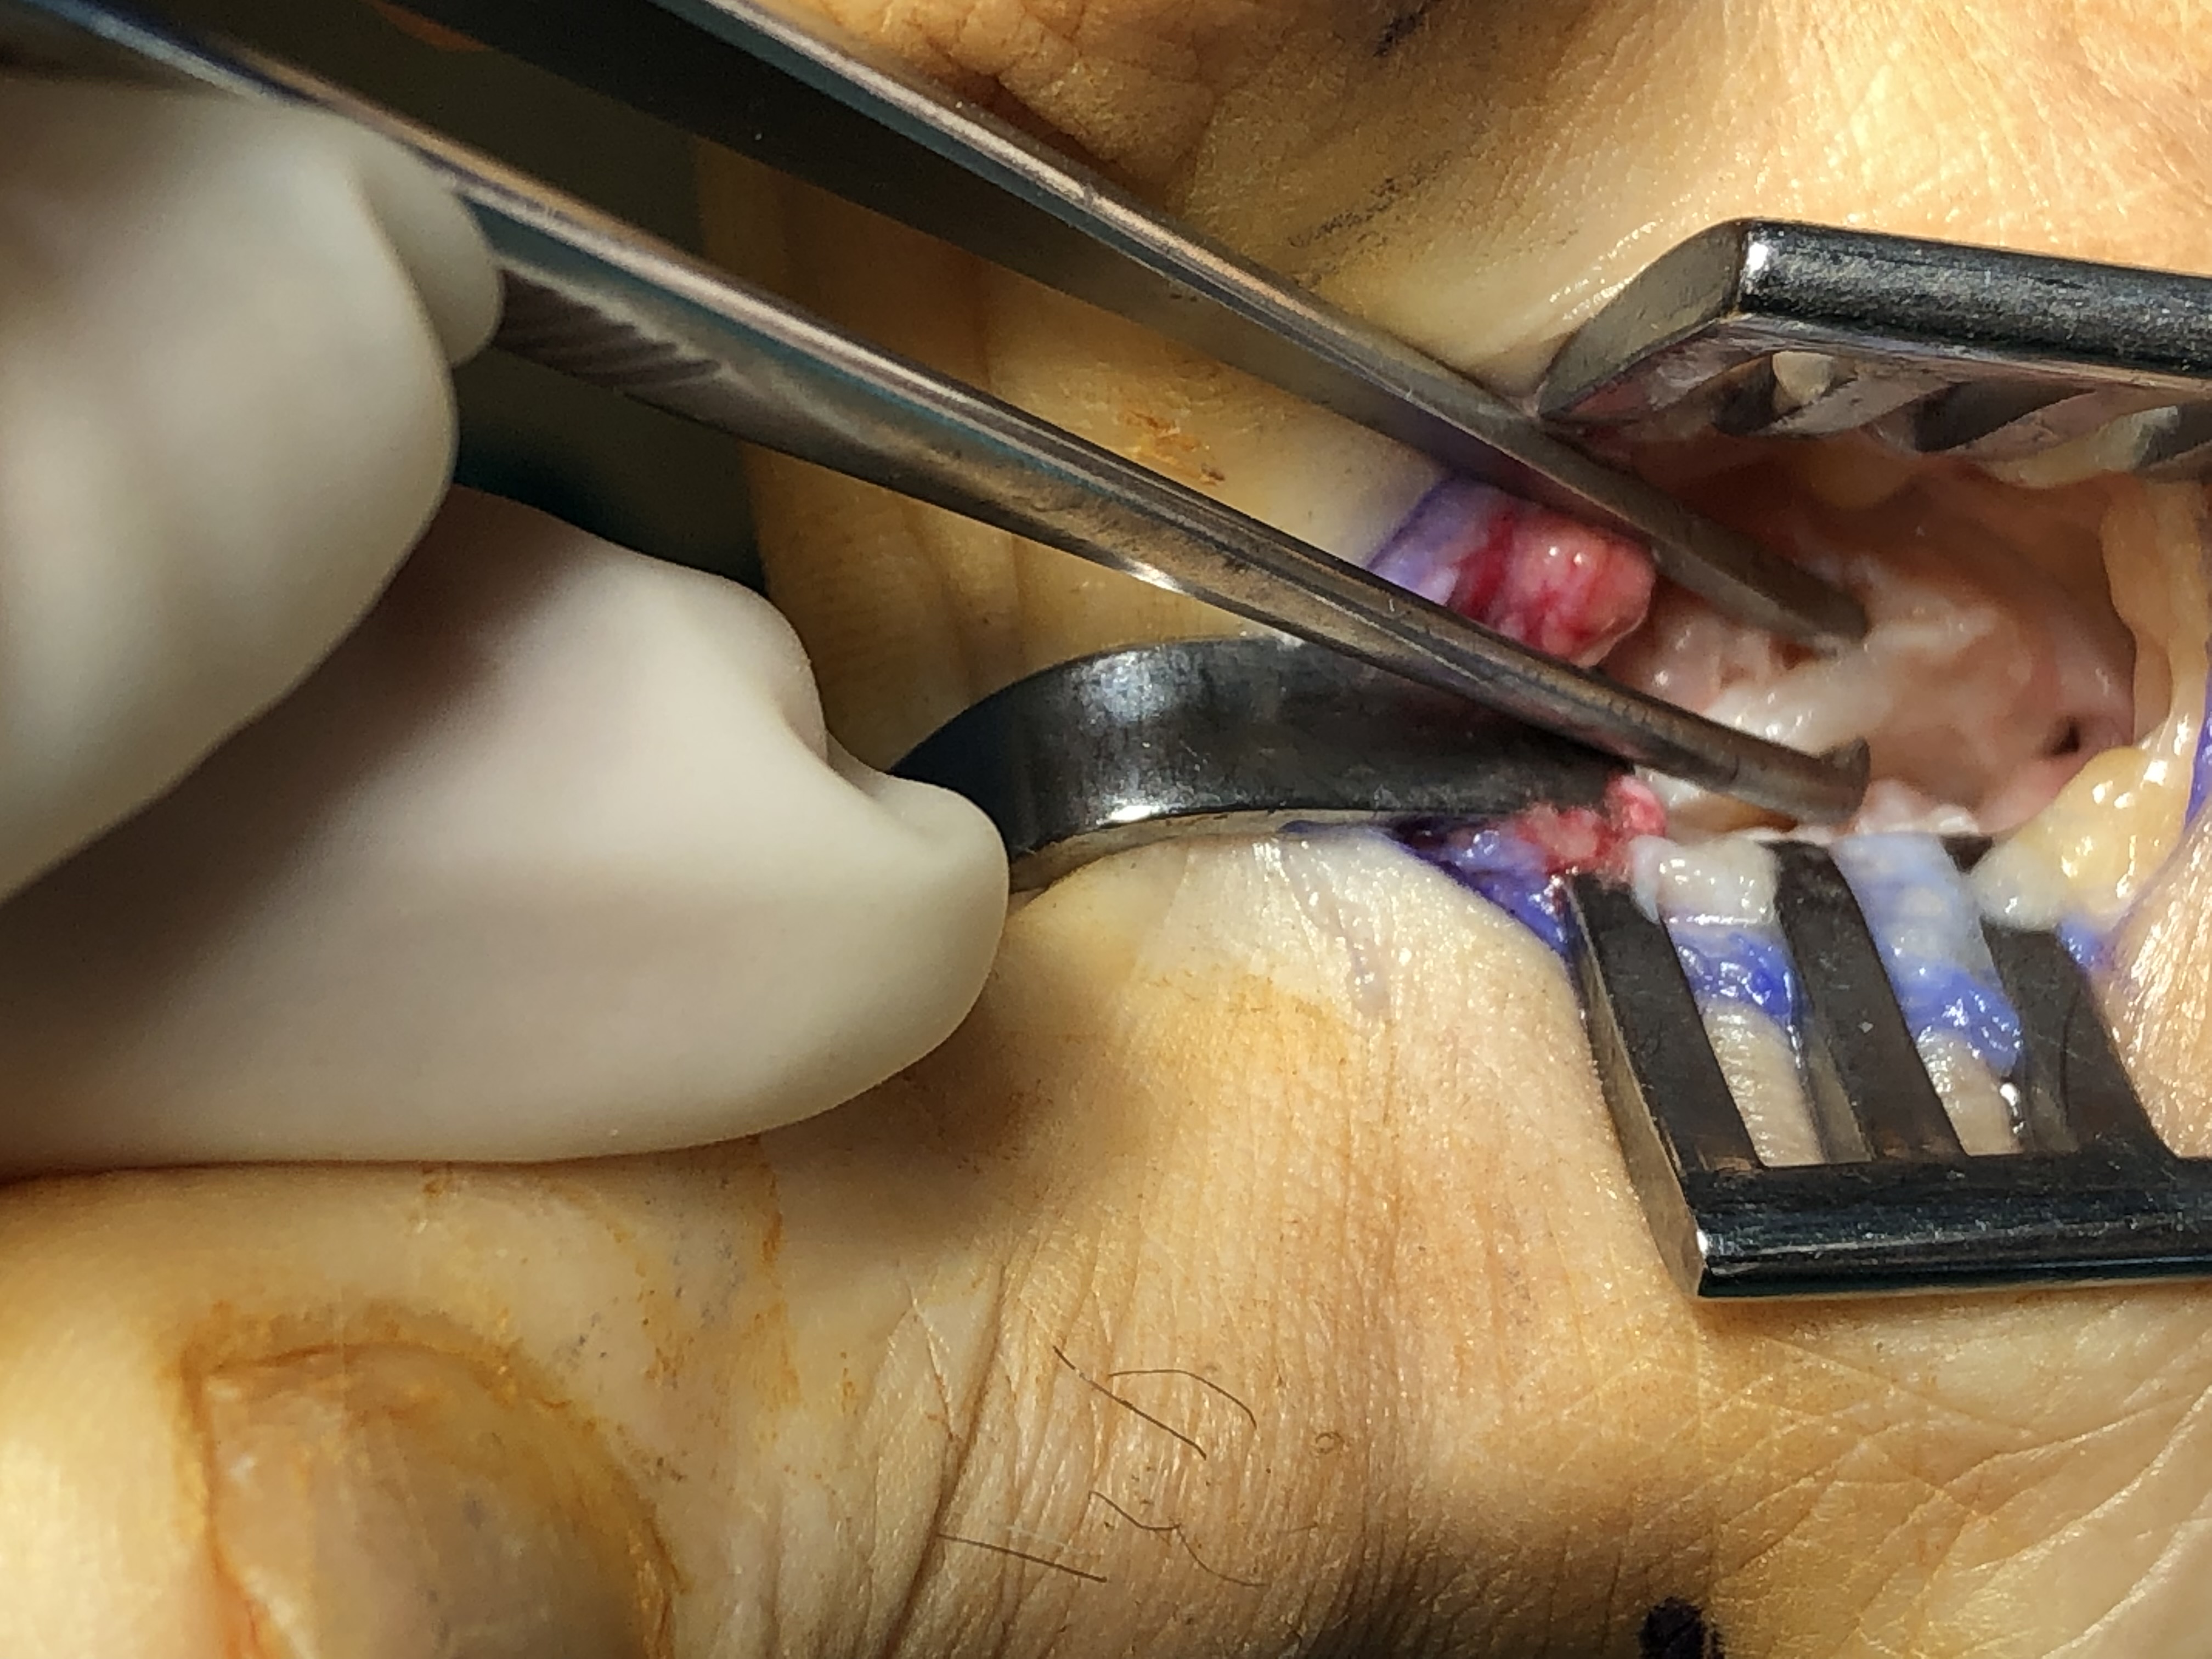

Έχουν περιγραφεί στην διεθνή βιβλιογραφία πάνω από 130 διαφορετικές χειρουργικές τεχνικές για την διόρθωση του βλαισού μεγάλου δακτύλου. Περιλαμβάνουν επεμβάσεις στα μαλακά μόρια της άρθρωσης (θύλακος, σύνδεσμοι, τένοντες) και στα οστά με διενέργεια διορθωτικών οστεοτομιών (σε διαφορα επίπεδα του πρώτου μεταταρσίου και της εγγύς φάλαγγας του μεγάλου δακτύλου). Η χρήση της πιο κατάλληλης τεχνικής και ο συνδυασμός αυτών καθορίζεται από τον βαθμό της παραμόρφωσης, από την ακτινολογικά της χαρακτηριστικά, αλλά και από τις δραστηριότητες του ασθενούς.

Οι επεμβάσεις πραγματοποιούνται με γενική ή περιοχική αναισθησία και ο ασθενήςείναι σε θέση να περπατήσει την ίδια ημέρα με τη χρήση κατάλληλων υποδημάτων χωρίς κάποιο επιπλέον βοήθημα. Σταδιακά επιστρέφει στις καθημερινές του δραστηριότητες, απαλλαγμένος πλήρως από τα συμπτώματα.